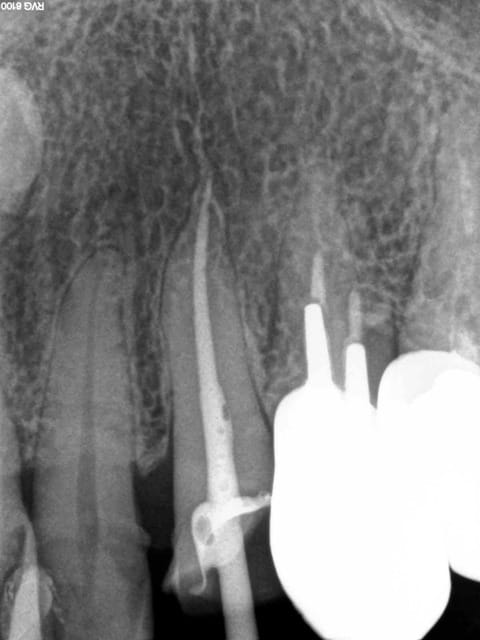

2 vo0nfp - Eugenol

3 cjxj6h - Eugenol

4 av1ldm - Eugenol

1 ynzexe - Eugenol

X ray 03 medium zvq18j - Eugenol